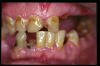

CM Caries, patología periodontal, desgaste.